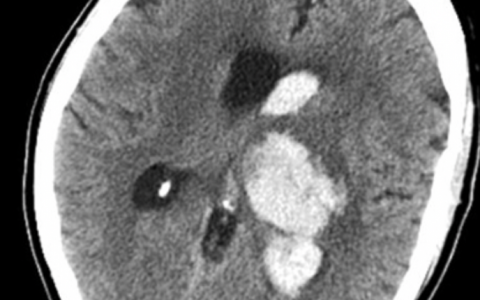

抗NMDA受体脑炎可能与12岁以上女性患者的肿瘤,特别是卵巢畸胎瘤有关。高达67%的患者脑MRI表现正常,脑电图在90%的患者中是异常的,但这些发现为非特异性改变。诊断有赖于脑脊液中NMDA受体抗体的存在来证实。